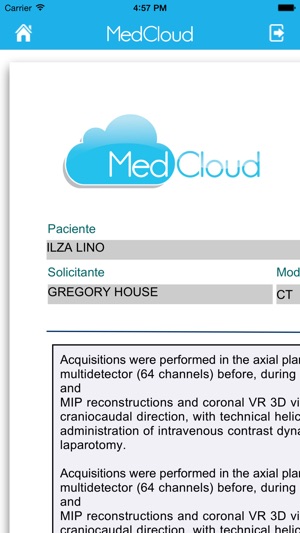

Através de uma plataforma centralizada, integrável e interativa, a MedCloud oferece conectividade e compatibilidade com todos os tipos de mídia, modalidades de exames e protocolos de integração voltados para sistemas de saúde.

Clinicas, hospitais, laboratórios, médicos, dentistas e demais empresas do segmento de saúde podem compartilhar trivialmente seus exames e informações de saúde com profissionais de saúde e pacientes, utilizando apenas uma conexão de Internet como requisito. Médicos, dentistas e pacientes podem interagir e compartilhar seus exames entre si, de forma prática e simples, além receberem opiniões de diferentes profissionais de saúde e manterem seu histórico médico online e seguro.